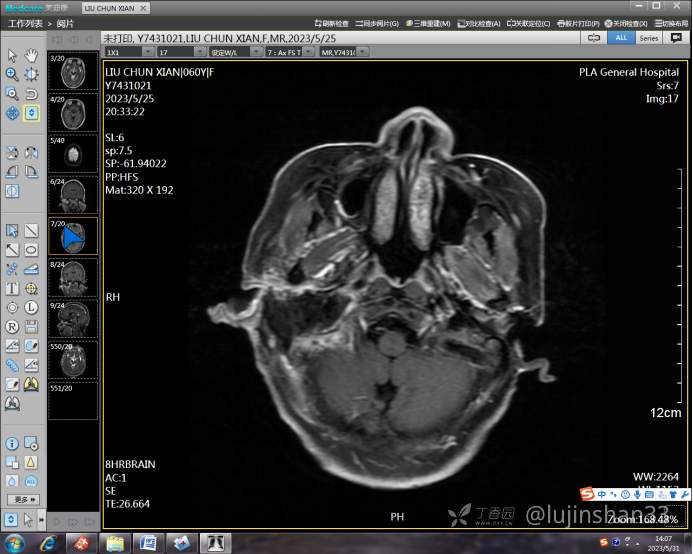

(2023-05-15 10:00,本院)行磁共振(颅脑)检查提示:右侧乳突区异常信号,考虑恶性、软骨来源肿瘤,软骨肉瘤可能性大。(集体讨论意见);脑内散在多发缺血灶。